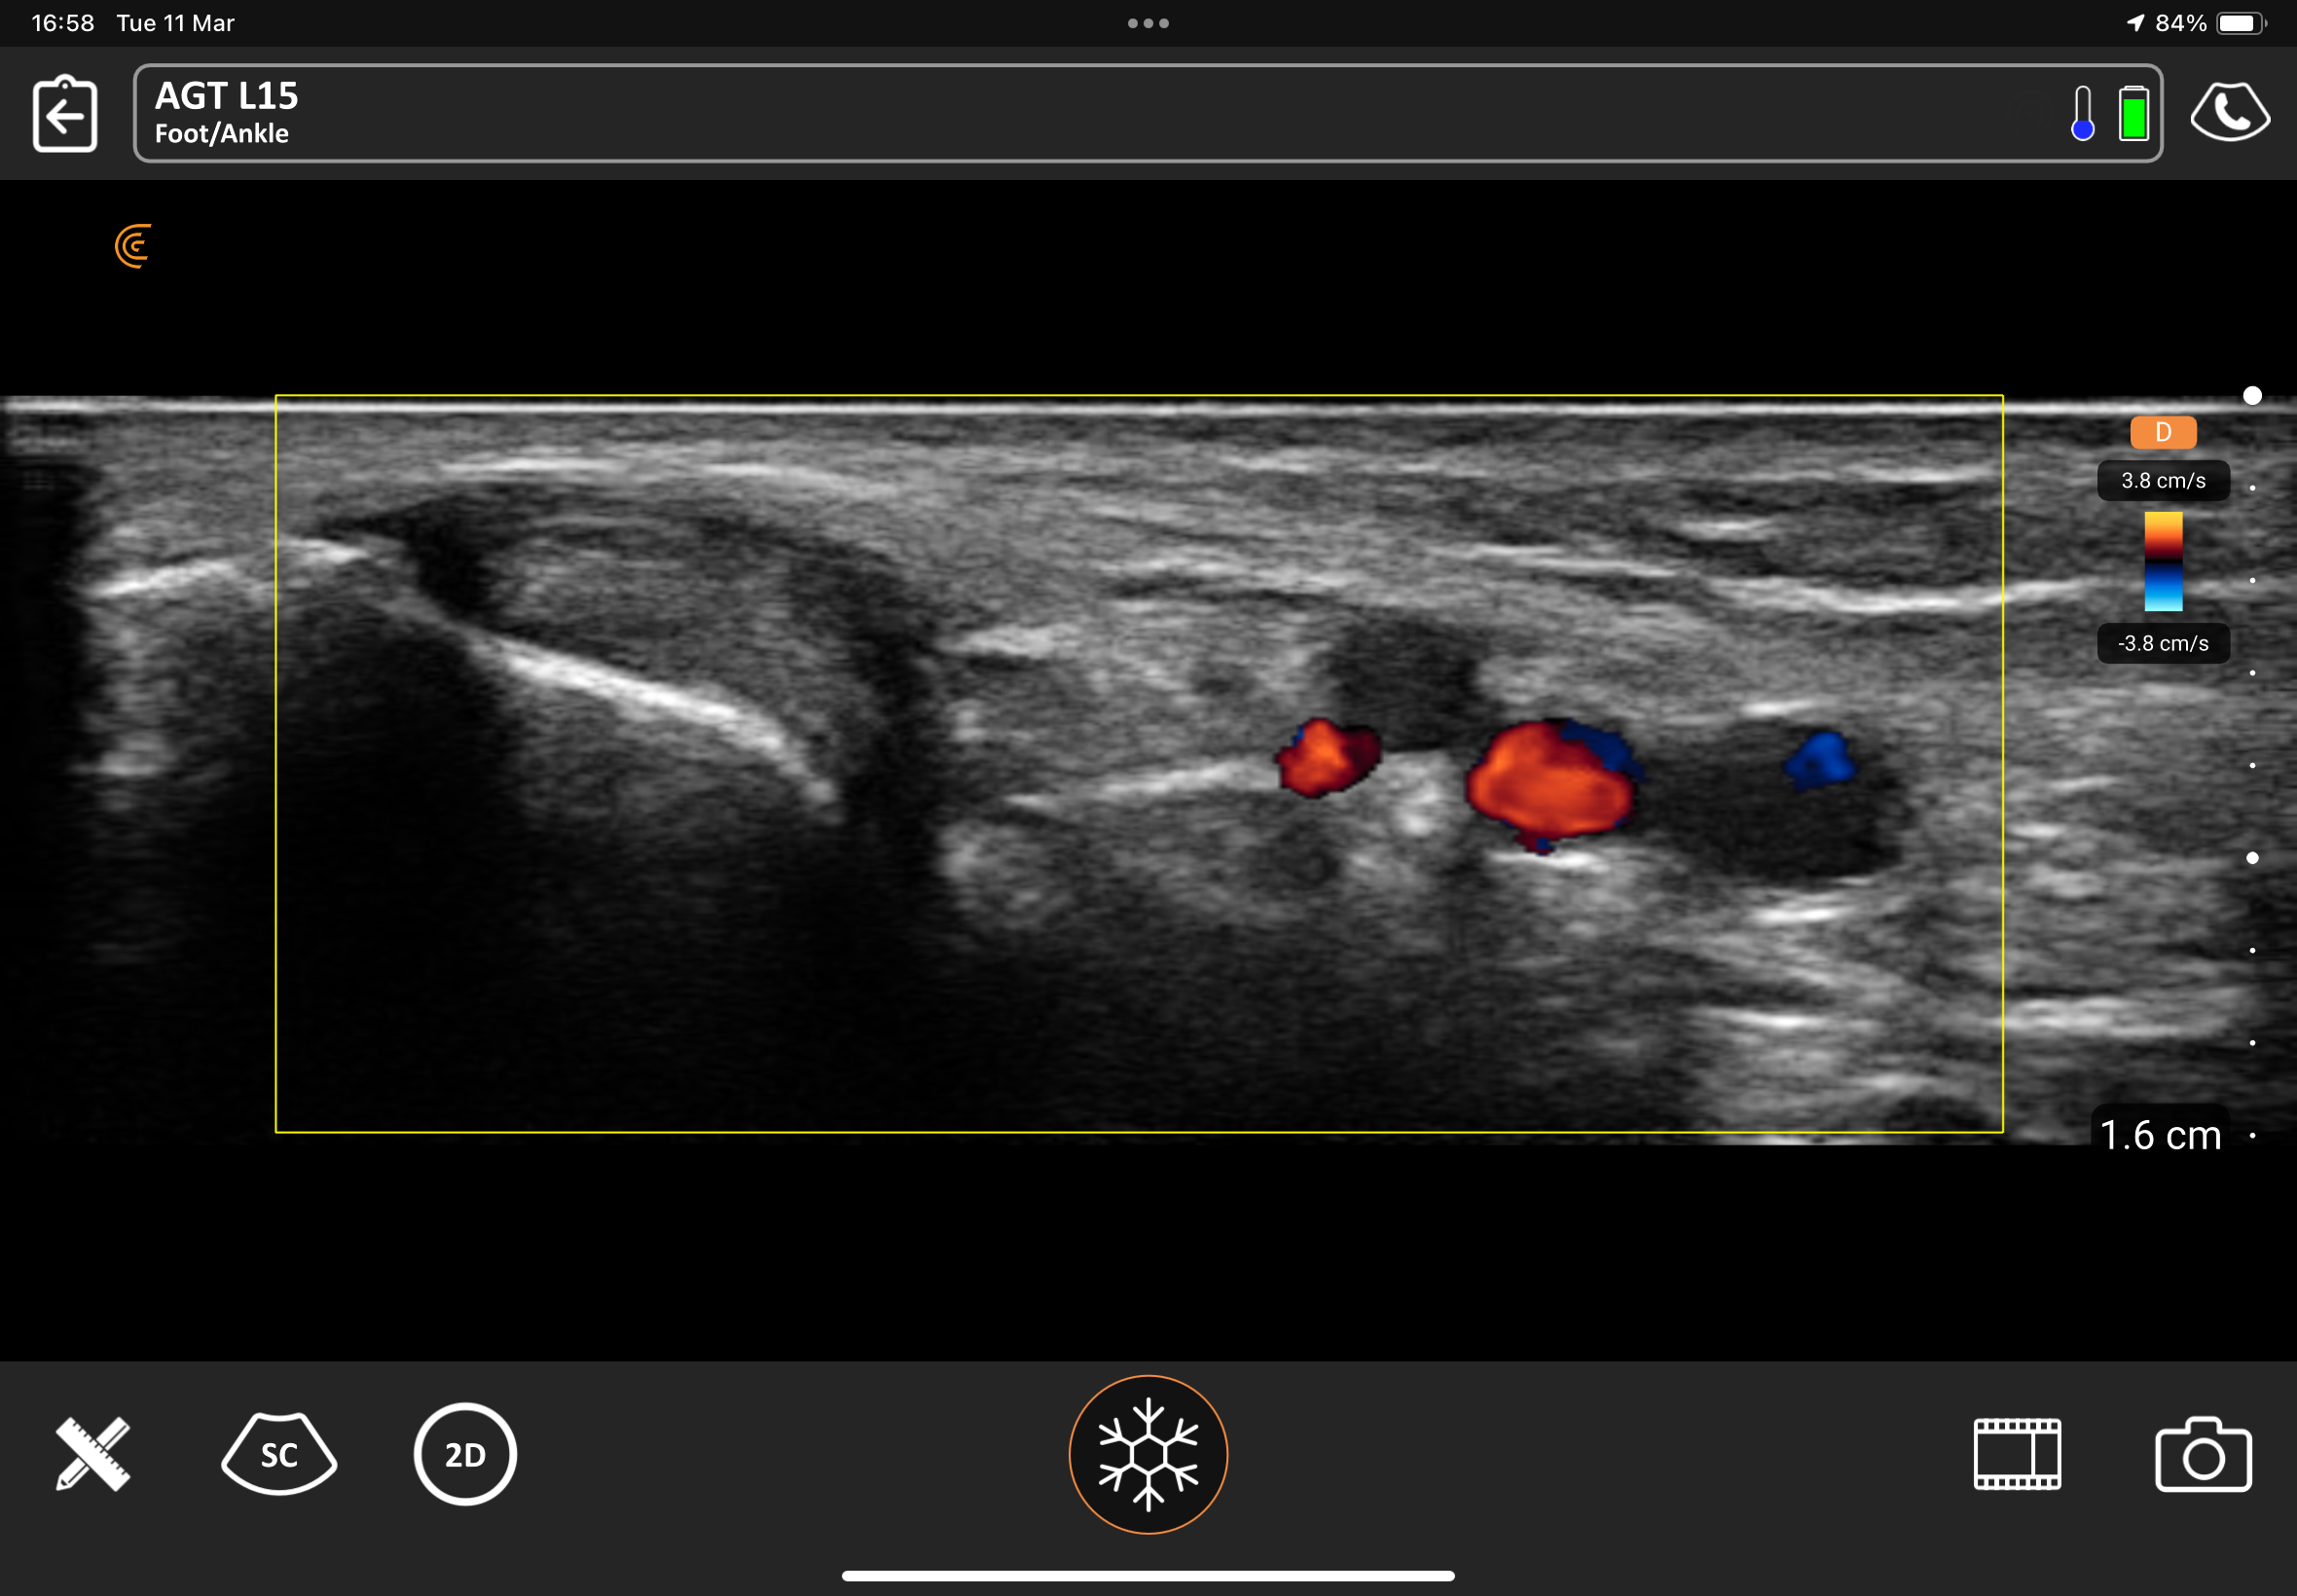

Ultrasound image of the foot and ankle showing blood flow in color Doppler.

Ultrasound of the foot and ankle is a safe, non-invasive imaging technique that provides detailed real-time views of soft tissues, muscles, tendons, ligaments, and joints. It helps diagnose conditions like tendon injuries, ligament sprains, arthritis, and nerve entrapments, offering a dynamic and radiation-free alternative to traditional imaging methods like X-rays or MRI.